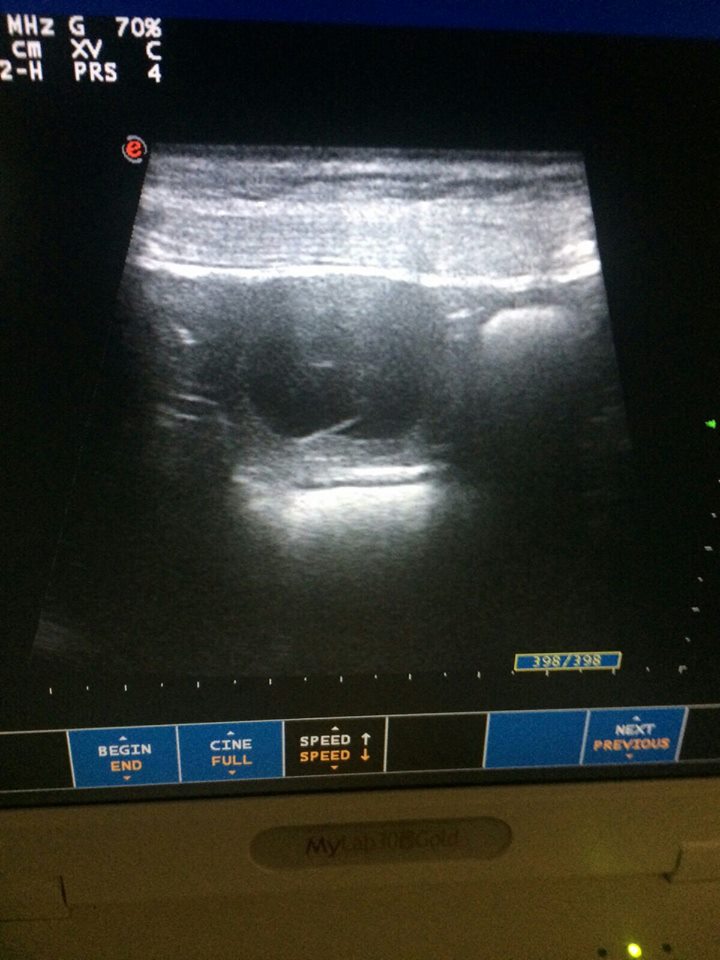

29/09/2015

Vandaag is er een echo gemaakt bij Nikita vom Hause Edelstein

En we hebben heel goed nieuws, ze is zwanger van Gromm Hof Chao!!!!!

De pups worden verwacht rond 05/11/2015.Voor meer info zie puppy's.